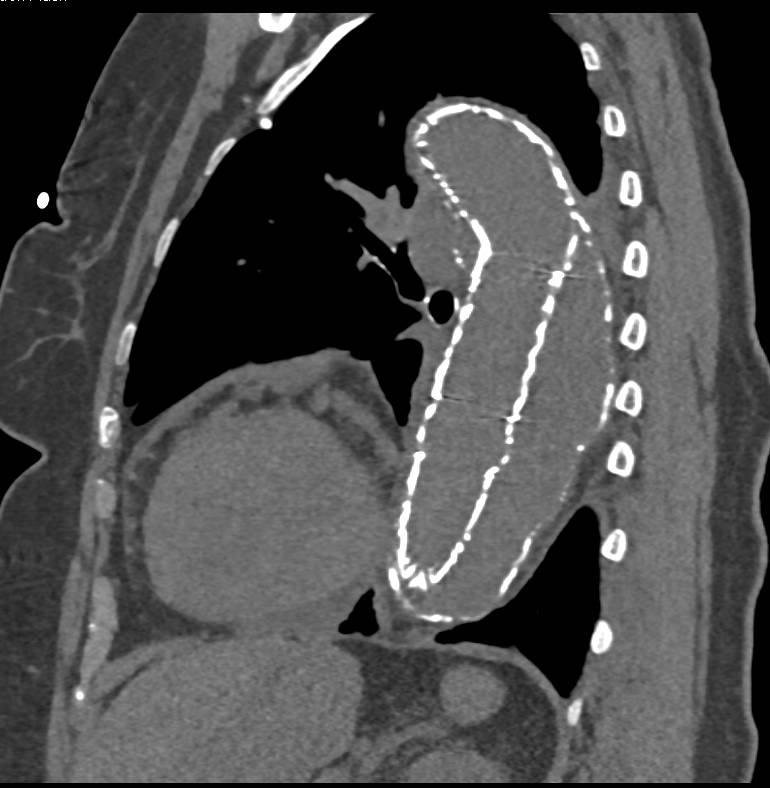

Linitis Plastica Stomach with Ascites Secondary to Breast Cancer Metastases